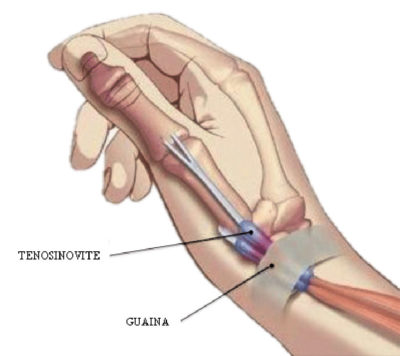

è una tendinite localizzata a livello del polso, alla base del pollice. Sono interessati i tendini abduttore lungo del pollice (che “divarica” il pollice dal palmo) ed il tendine estensore breve del pollice (che stende la prima parte del pollice).

è una tendinite localizzata a livello del polso, alla base del pollice. Sono interessati i tendini abduttore lungo del pollice (che “divarica” il pollice dal palmo) ed il tendine estensore breve del pollice (che stende la prima parte del pollice).